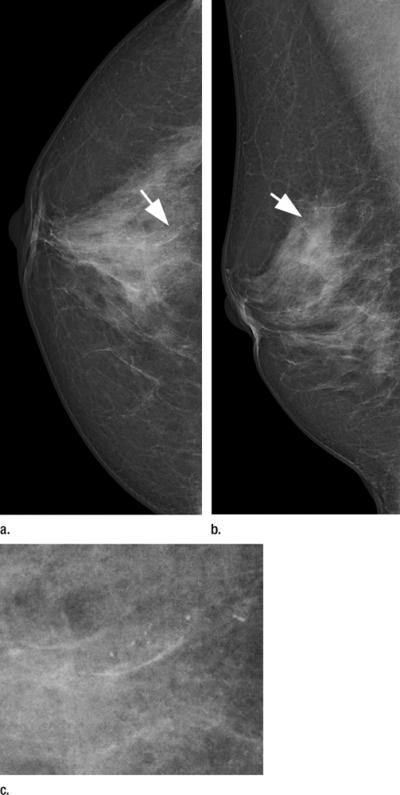

As mammography screening has shifted to digital technology, a range of computed radiography (CR) and direct radiography (DR) systems have emerged. The photon-counting technique is a promising DR approach that uses a unique detector to decrease scattered radiation and noise, enabling dose reduction and making it a promising tool for screening.

The DR photon-counting scan system had a cancer detection rate of 0.76 percent for subsequent screening, compared with 0.59 percent for the other screening units. The recall rate was 5.4 percent for the photon-counting method and 3.4 percent for the other methods.

The photon-counting technique had almost twice the detection rate of other methods for ductal carcinoma in situ (DCIS), an early, noninvasive form of disease. It had a higher DCIS detection rate than the statewide units and the conventional DR subgroup.

The photon-counting technique also offers lateral dose modulation during the image acquisition, which can help account for differences in breast density. Cancer often is more difficult to detect in women with dense breasts.